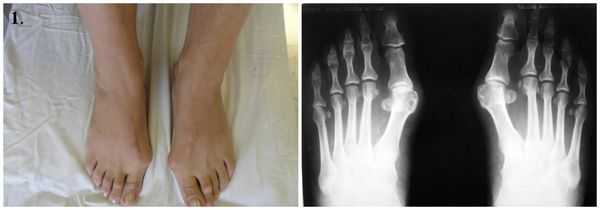

Вальгусная деформация стопы - это патология, сопровождающаяся уплощением стоп и их «заваливанием» кнутри. В области голеностопных суставов и стоп образуется вальгусное (Х-образное) искривление, пятка опирается на поверхность своим внутренним краем. В положении стоя при сведенных вместе выпрямленных ногах пятки располагаются на расстоянии 4 и более сантиметров друг от друга. Диагноз выставляется на основании осмотра, плантографии, рентгенографии и подометрии. Лечение на начальных стадиях консервативное, включает в себя физиотерапию и ношение ортопедической обуви. При выраженном искривлении выполняется хирургическая коррекция.

Вальгусная деформация стопы - искривление оси стопы, при котором средний отдел стопы опускается, пятка разворачивается кнаружи, ее внутренний край также опускается. При положении больного стоя со сведенными ногами видна Х-образная деформация в области голеностопных суставов и задних отделов стопы - при соприкасающихся внутренних лодыжках пятки расположены на значительном расстоянии друг от друга. Патология обычно возникает в раннем детском возрасте. У взрослых может развиваться вследствие усугубления плоскостопия, а также под воздействием различных травматических и нетравматических факторов.

Диагноз вальгусная деформация стопы выставляется на основании внешних признаков и данных инструментальных исследований. При внешнем осмотре врач обращает внимание на уплощение сводов стопы, выпячивание внутренней и сглаживание наружной лодыжки, а также отклонение пятки кнаружи. Для подтверждения диагноза и определения степени деформации выполняется плантография, рентгенография стоп и подометрия.

На рентгенограммах выявляется уменьшение высоты свода стопы, нарушение взаиморасположения переднего, среднего и заднего отделов стопы, а также отдельных костей в суставах предплюсны. Подометрия используется для оценки распределения нагрузки на стопу. Компьютерная плантография применяется для расчета углов, параметров и индексов, позволяющих определить наличие и тип плоскостопия.

Вальгусная деформация стопы у ребенка может быть заподозрена педиатром, однако окончательно судить о наличии патологии и степени ее выраженности позволяет только осмотр ребенка детским травматологом-ортопедом и специальное обследование. При осмотре ребенка обращает внимание отклонение пальцев и пятки кнаружи, сглаживание сводов и смещение внутренней части стопы - внутрь.

Для окончательного решения вопросов диагностики у ребенка вальгусной деформации стопы проводится рентгенография стоп, компьютерная плантография и подометрия. На рентгенограммах стоп, выполненных в 3-х проекциях, удается увидеть изменение положения стоп относительно друг друга. Компьютерная плантография позволяет рассчитать различные морфологические параметры стопы. С помощью подометрии оценивается распределение нагрузки на разные отделы стопы. Компьютерная подометрия позволяет выявить изменения, когда клинические признаки вальгусной деформации стопы у детей еще не проявились. В ряде случаев с уточняющей целью может потребоваться проведение УЗИ суставов.